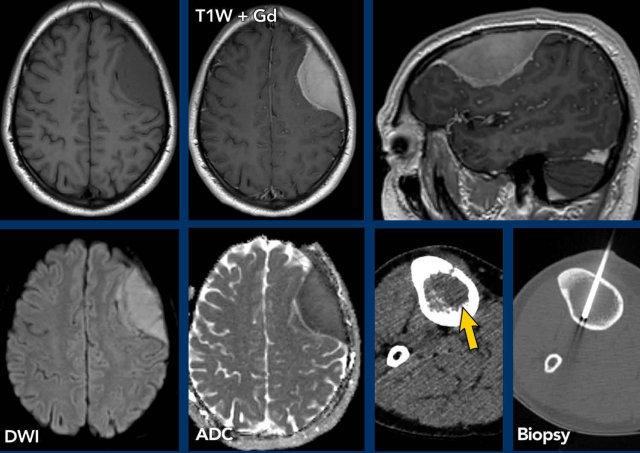

These images are of a 63-year old patient.

Images

CT shows a dense periventricular

lesion with surrounding edema.

On the T2W-image the lesion has a relatively low density. There is homogeneous enhancement of the lesion with multiple periventricular enhancing

lesions.

The density on the CT and the distribution are highly suggestive of lymphoma.

Lymphoma

These images are of a 76-year old woman, who was confused after a fall.

First look at the images and then continue reading.

Question:

- What is the most likely diagnosis?

- Which findings are typical for this diagnosis?

The findings are:

- Hyperdense lesion on the NECT with some vasogenic edema.

- MR shows multiple lesions with solid enhancement and diffusion restriction.

- On T2W the lesions show a low signal intensity

- One lesion is located in the corpus callosum and another one is periventricular.

All these findings are typical for a primary CNS lymphoma, which is different from a systemic lymphoma.

These tumors make up for 6-7% of all CNS tumors and the histology is a B-cel NHL.

They are mostly located periventricular subependymal, in the corpus callosum and in the basal ganglia.

Always think lymphoma in a solid enhancing lesion which is located near the ventricles.

The hyperdense appearance on CT and the slight hypointensity on T2W-imaging, as well as the restricted diffusion are attributed to the dense cellularity of the lymphomatous tissue.

In immuno-compromised patients the enhancement can be ring-like.

This patient has a lot of edema, but in many cases the edema is very limited.